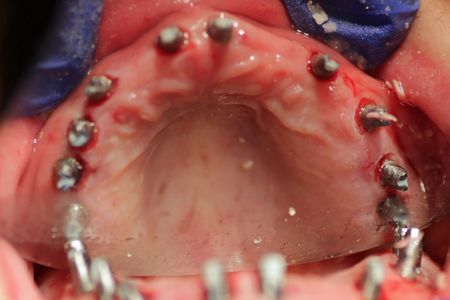

Dr. Gibney surgically implants 10 posts on the top and then 10 posts on the bottom.

After surgery, Dr. Gibney takes CAT scan images and impressions to review the implant surgery and create her temporary teeth. Immediately after, Cristina is sent home to rest.